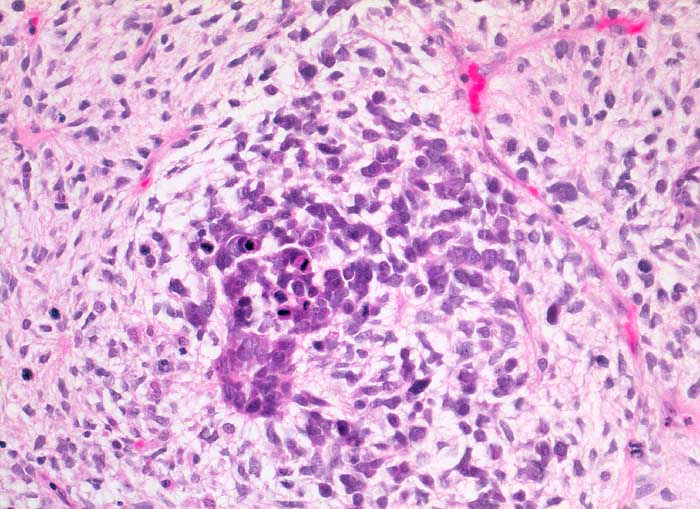

PathoPic ID 5385 - maligner Müller'scher Mischtumor: Sarkomkomponente

maligner Müller'scher Mischtumor: Sarkomkomponente

Sarkomatöse Komponente mit zahlreichen Mitosen

Ovarialkarzinom

Histologie

200